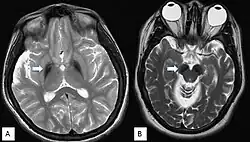

Da die Symptome meist unspezifisch sind, ist eine gesicherte Diagnose nur über bildgebende Verfahren und genetische Sequenzierung möglich. Im fortgeschrittenen Stadium sind mittels Magnetresonanztomographie Veränderungen in der Substantia nigra sowie im Globus pallidus erkennbar, die durch die Anlagerung von Eisen entstehen.[9][25] Frühe Anzeichen vor dem Auftreten von nachweisbaren Eisenablagerungen könnten ein Anschwellen der Substantia nigra sowie eine Hyperintensität in einer T2-gewichteten MRT-Aufnahme des Nucleus dentatus sein.[26] Letztendlich kann die Diagnose jedoch nur durch die Identifizierung der Mutation des WDR45-Gens abgesichert werden. Zur Diagnose der häufig auftretenden Epilepsie sind EEGs angezeigt.